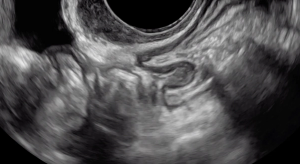

A hypoechoic deep endometriosis nodule is noted within the hyperechoic uterosacral ligament, infiltrating the parametrium

A hypoechoic deep endometriosis nodule is noted within the hyperechoic uterosacral ligament.

A hypoechoic deep endometriosis nodule is noted within the hyperechoic uterosacral ligament. In this case, there is an ovary containing an endometrioma fixed to the uterosacral ligament nodule.